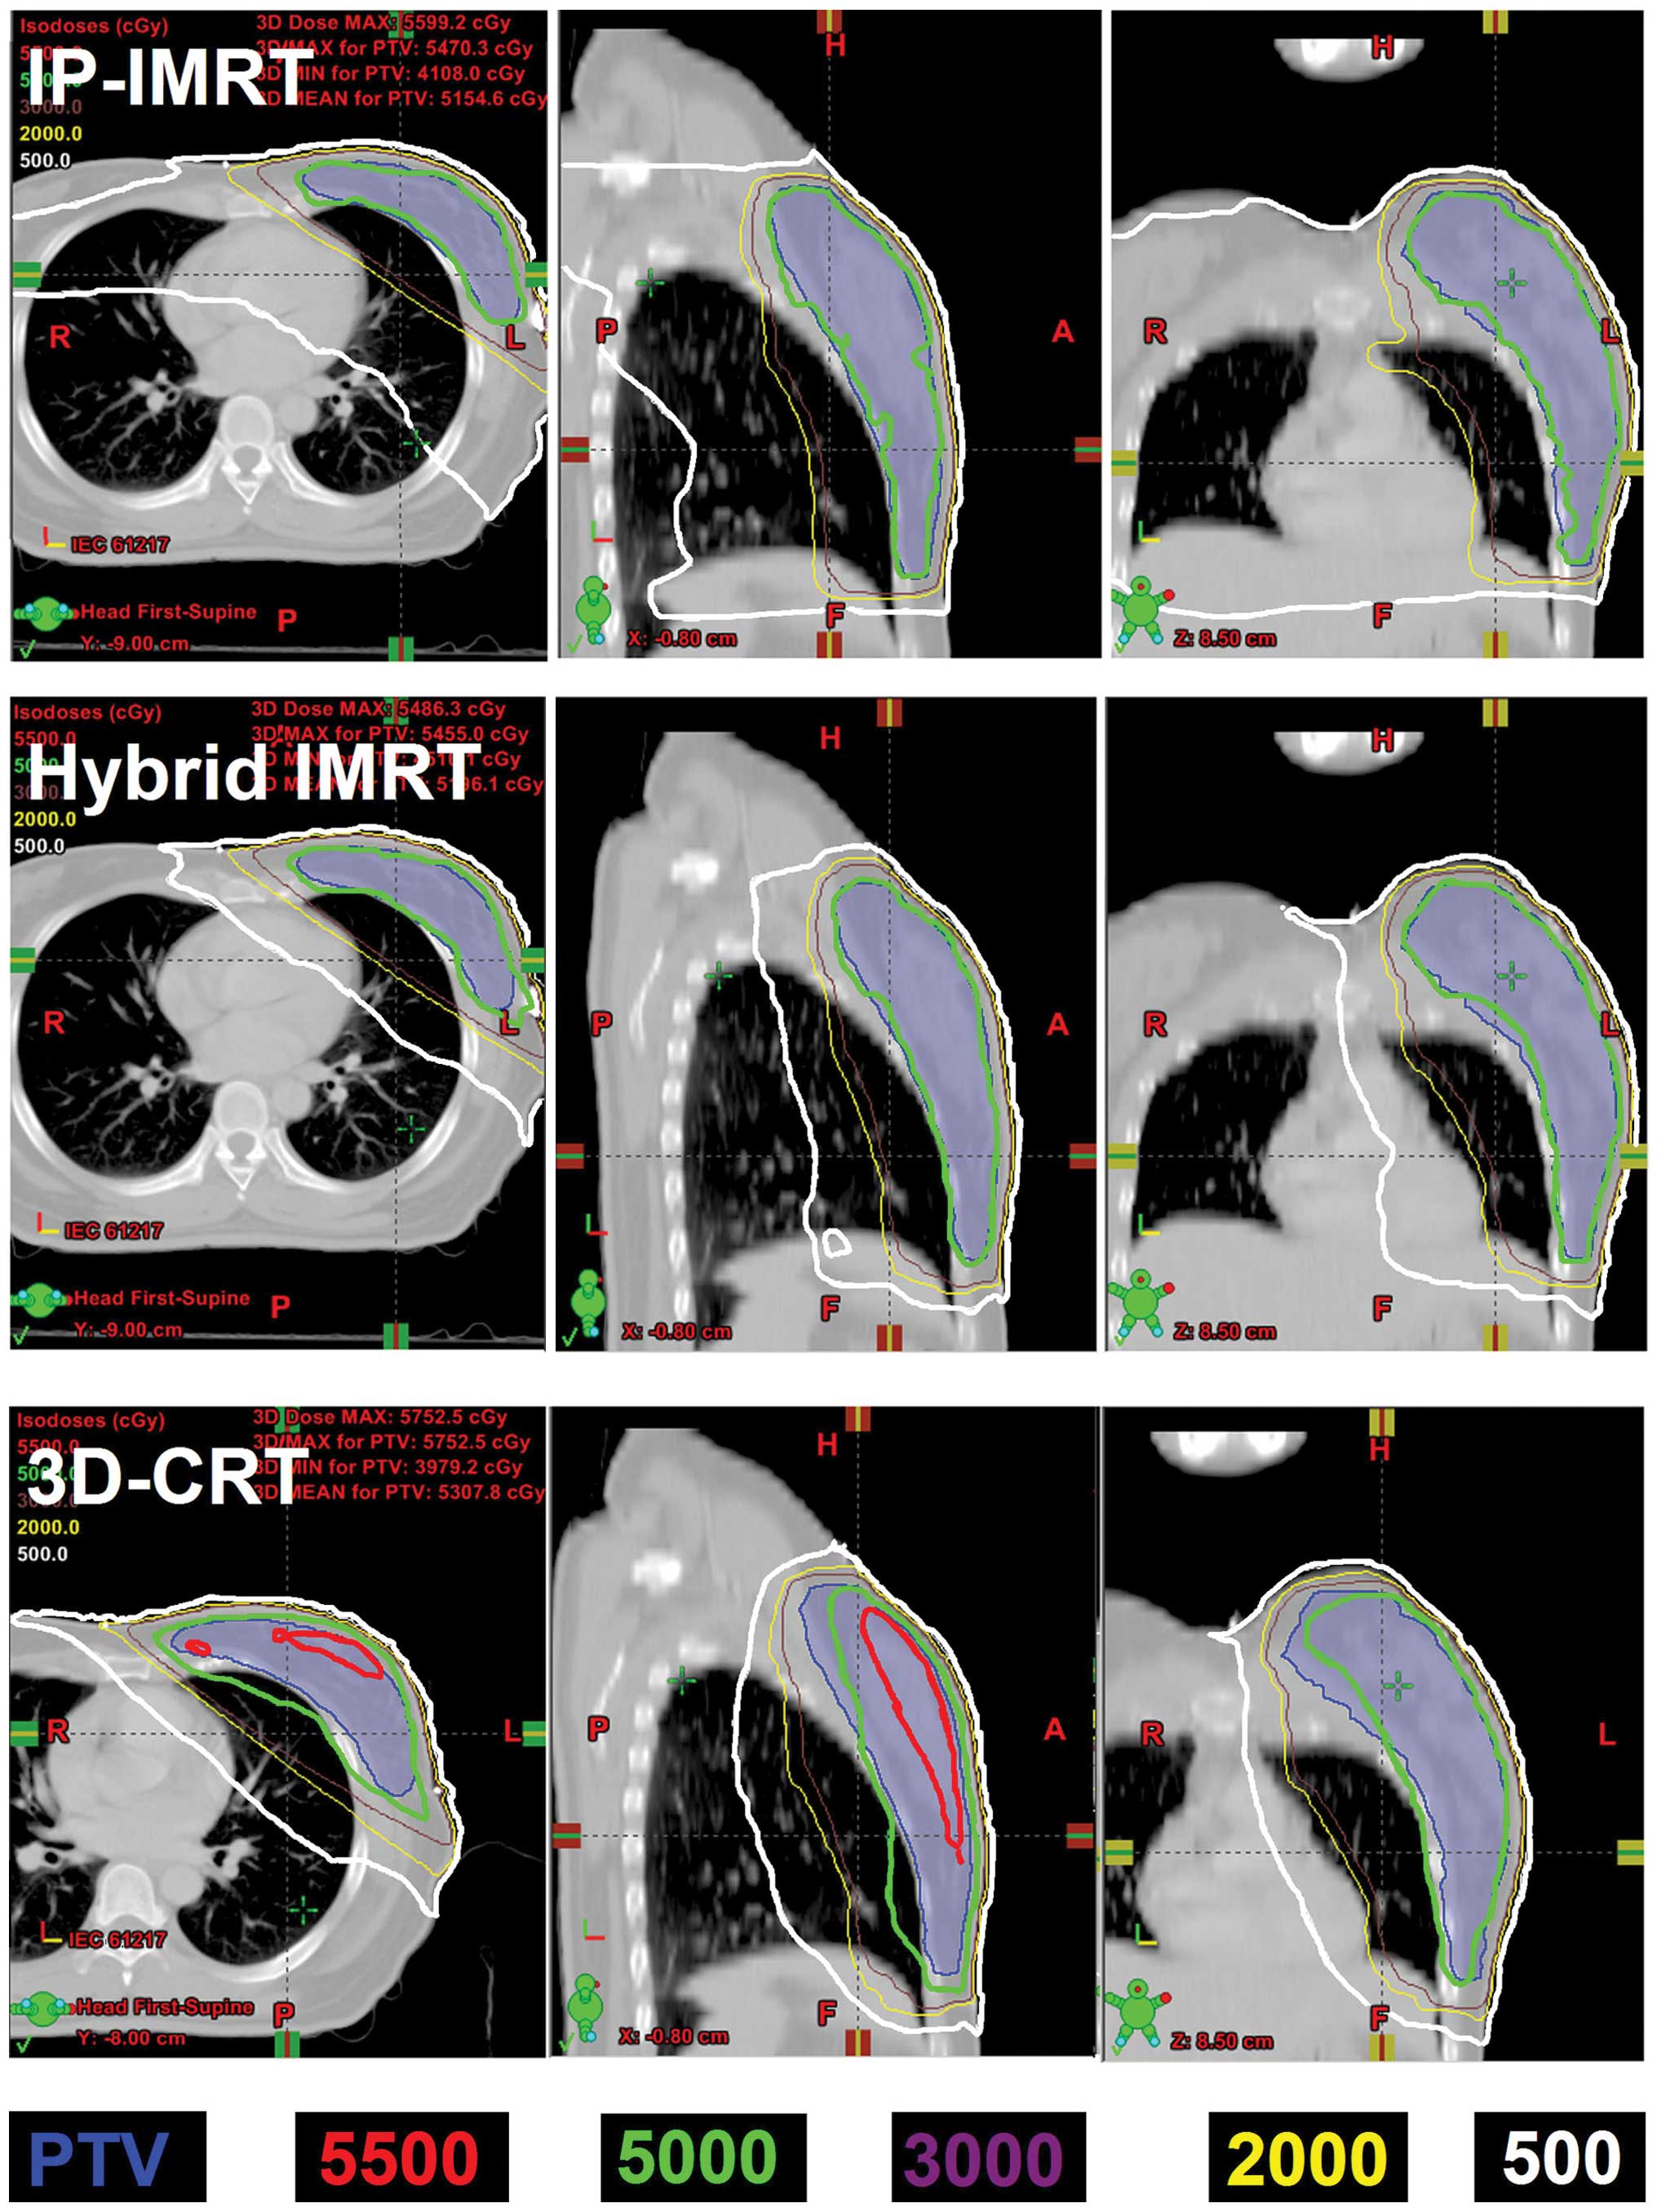

Ap Pa Field Orientation Followed By Imrt Reduces Lung Exposure In